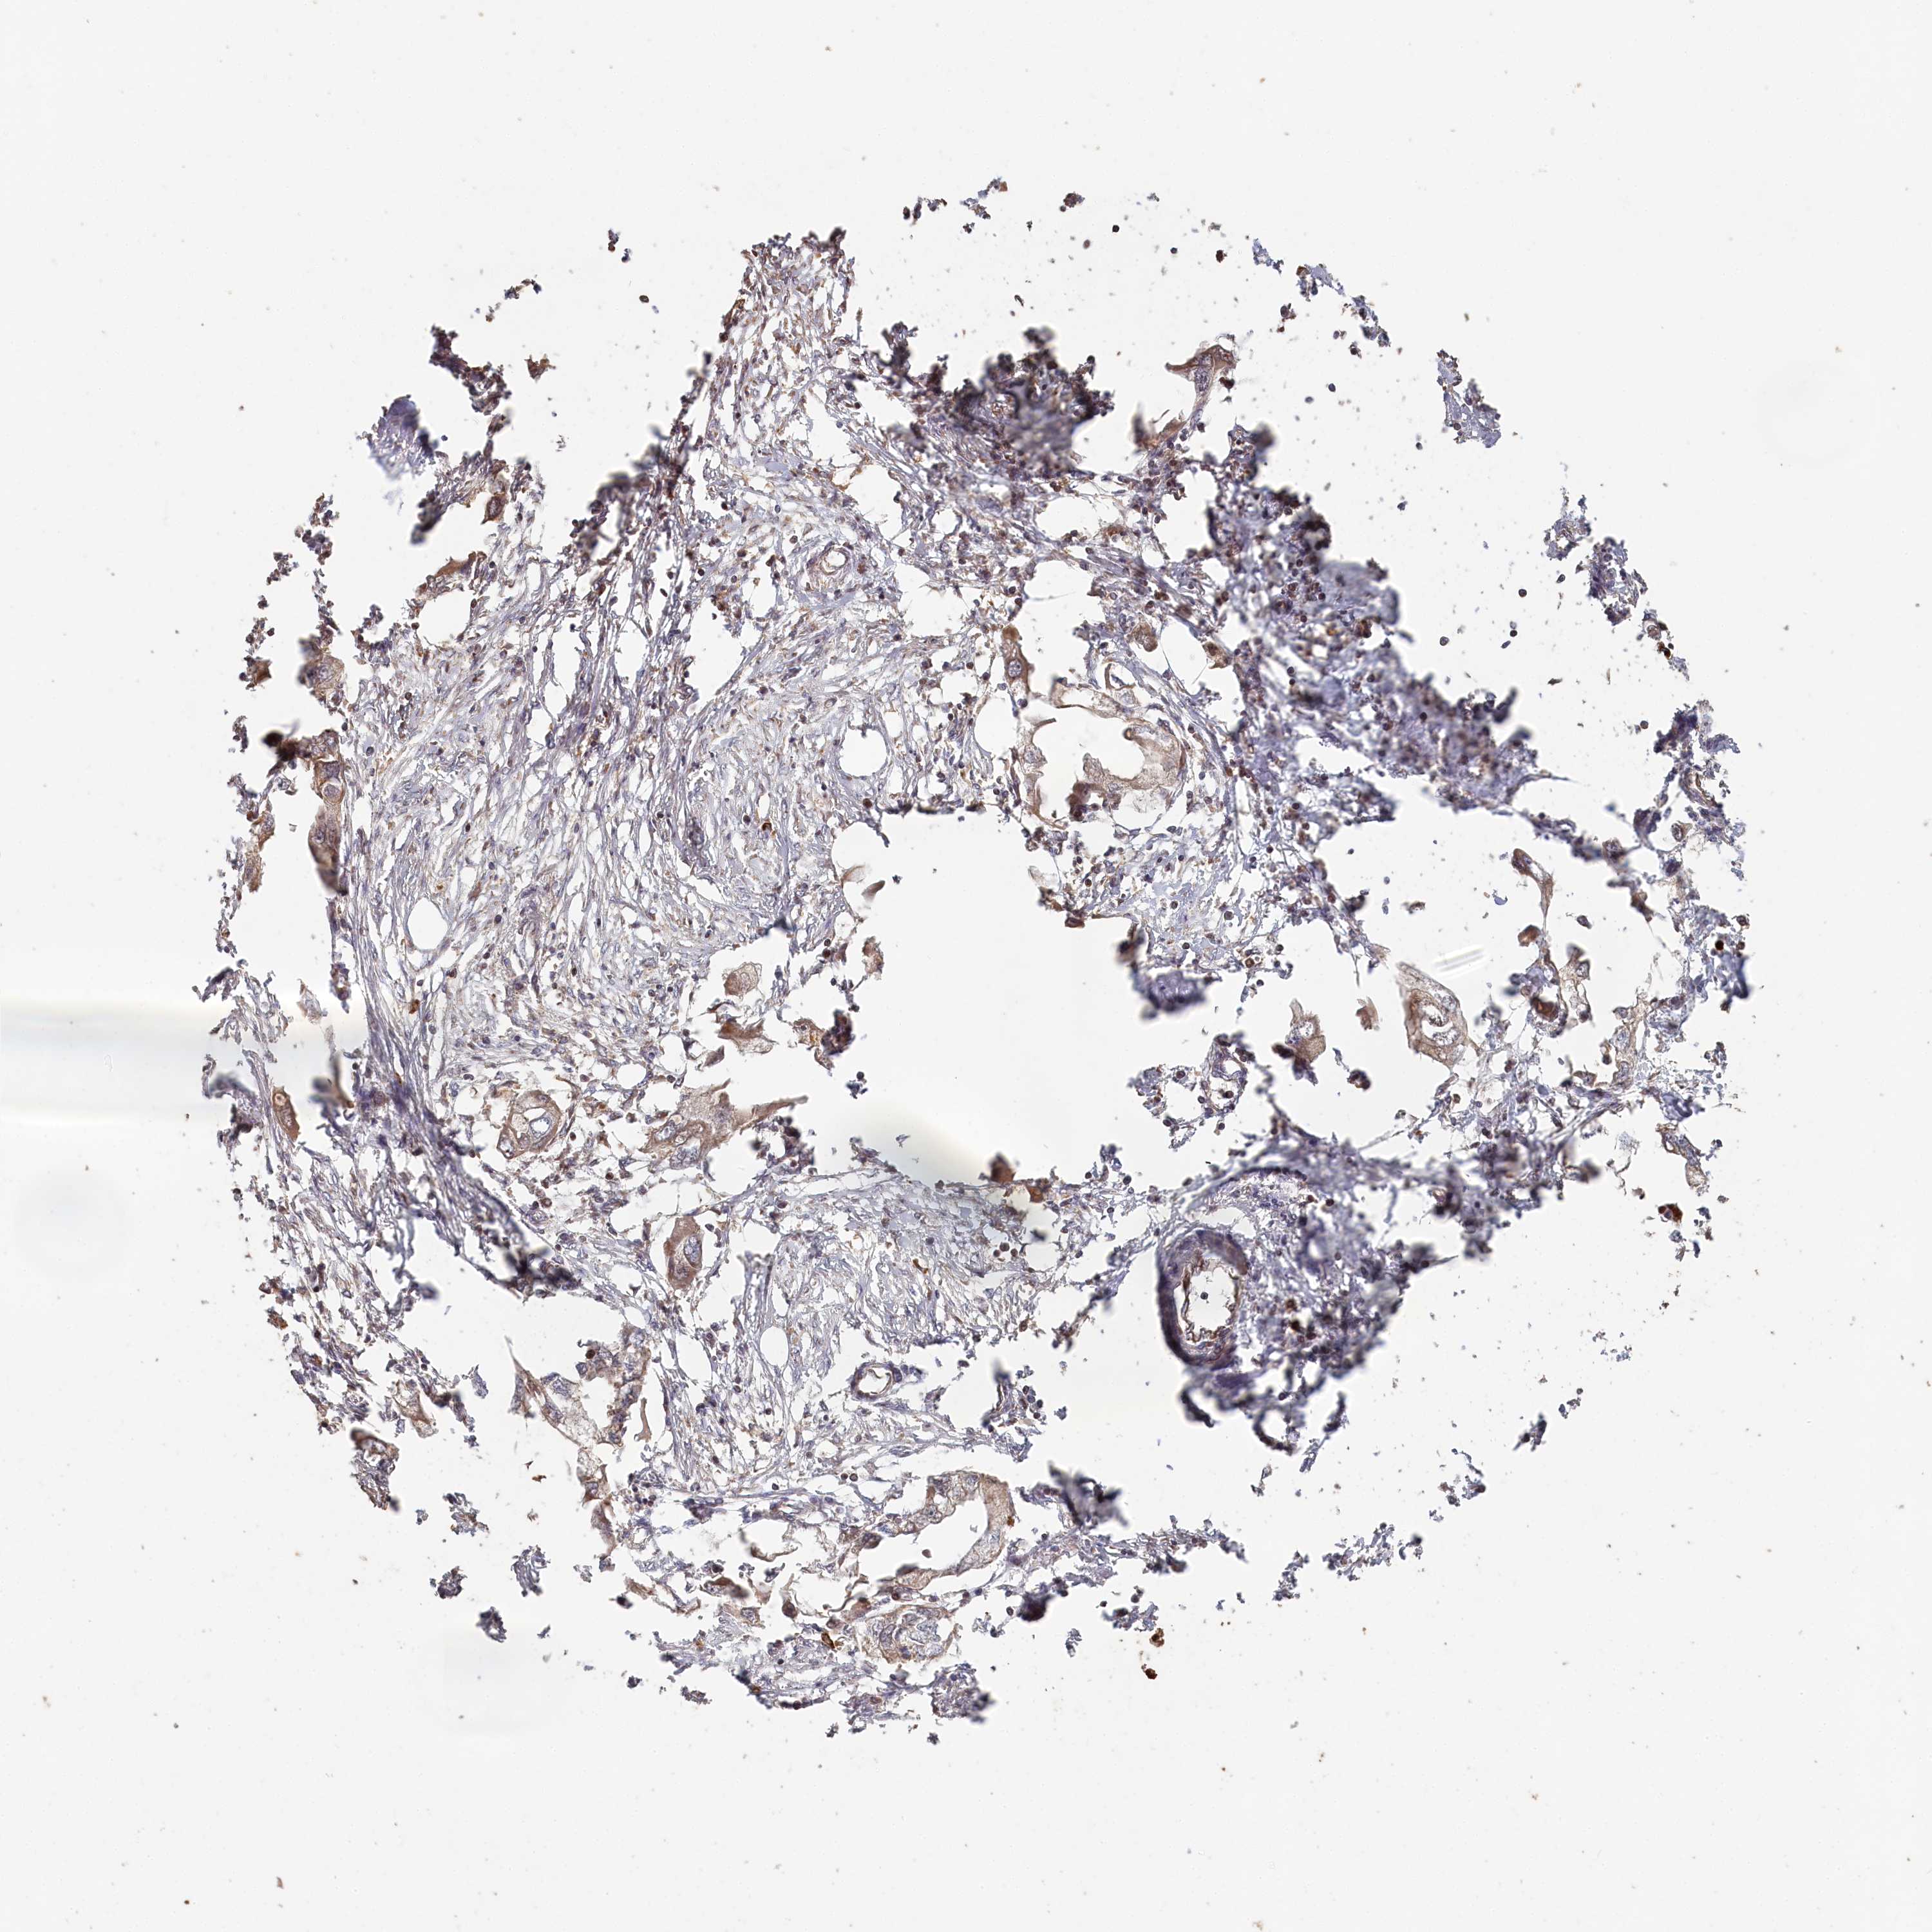

ENDOMETRIAL CANCER - Protein expressioni

A mouse-over function shows sample information and annotation data. Click on an image to view it in a full screen mode. Samples can be filtered based on level of antibody staining by selecting one or several of the following categories: high, medium, low and not detected. The assay and annotation is described here.

Note that samples used for immunohistochemistry by the Human Protein Atlas do not correspond to samples in the TCGA dataset.

Antibody stainingi

Antibody staining in the annotated cell types in the current human tissue is reported as not detected, low, medium, or high, based on conventional immunohistochemistry profiling in selected tissues. This score is based on the combination of the staining intensity and fraction of stained cells.

Each image is clickable and will lead to virtual microscopy that enables deeper exploration of all samples and also displays staining intensity scores, fraction scores and subcellular localization as well as patient and tissue information for each sample.

Antibody HPA038547

Antibody HPA038548

Staining

High

Medium

Low

Not detected

Intensity

Strong

Moderate

Weak

Negative

Quantity

>75%

75%-25%

<25%

None

Location

Nuclear

Cytoplasmic/membranous

Cytoplasmic/membranous,nuclear

Adenocarcinoma, NOS

Adenocarcinoma, metastatic, NOS